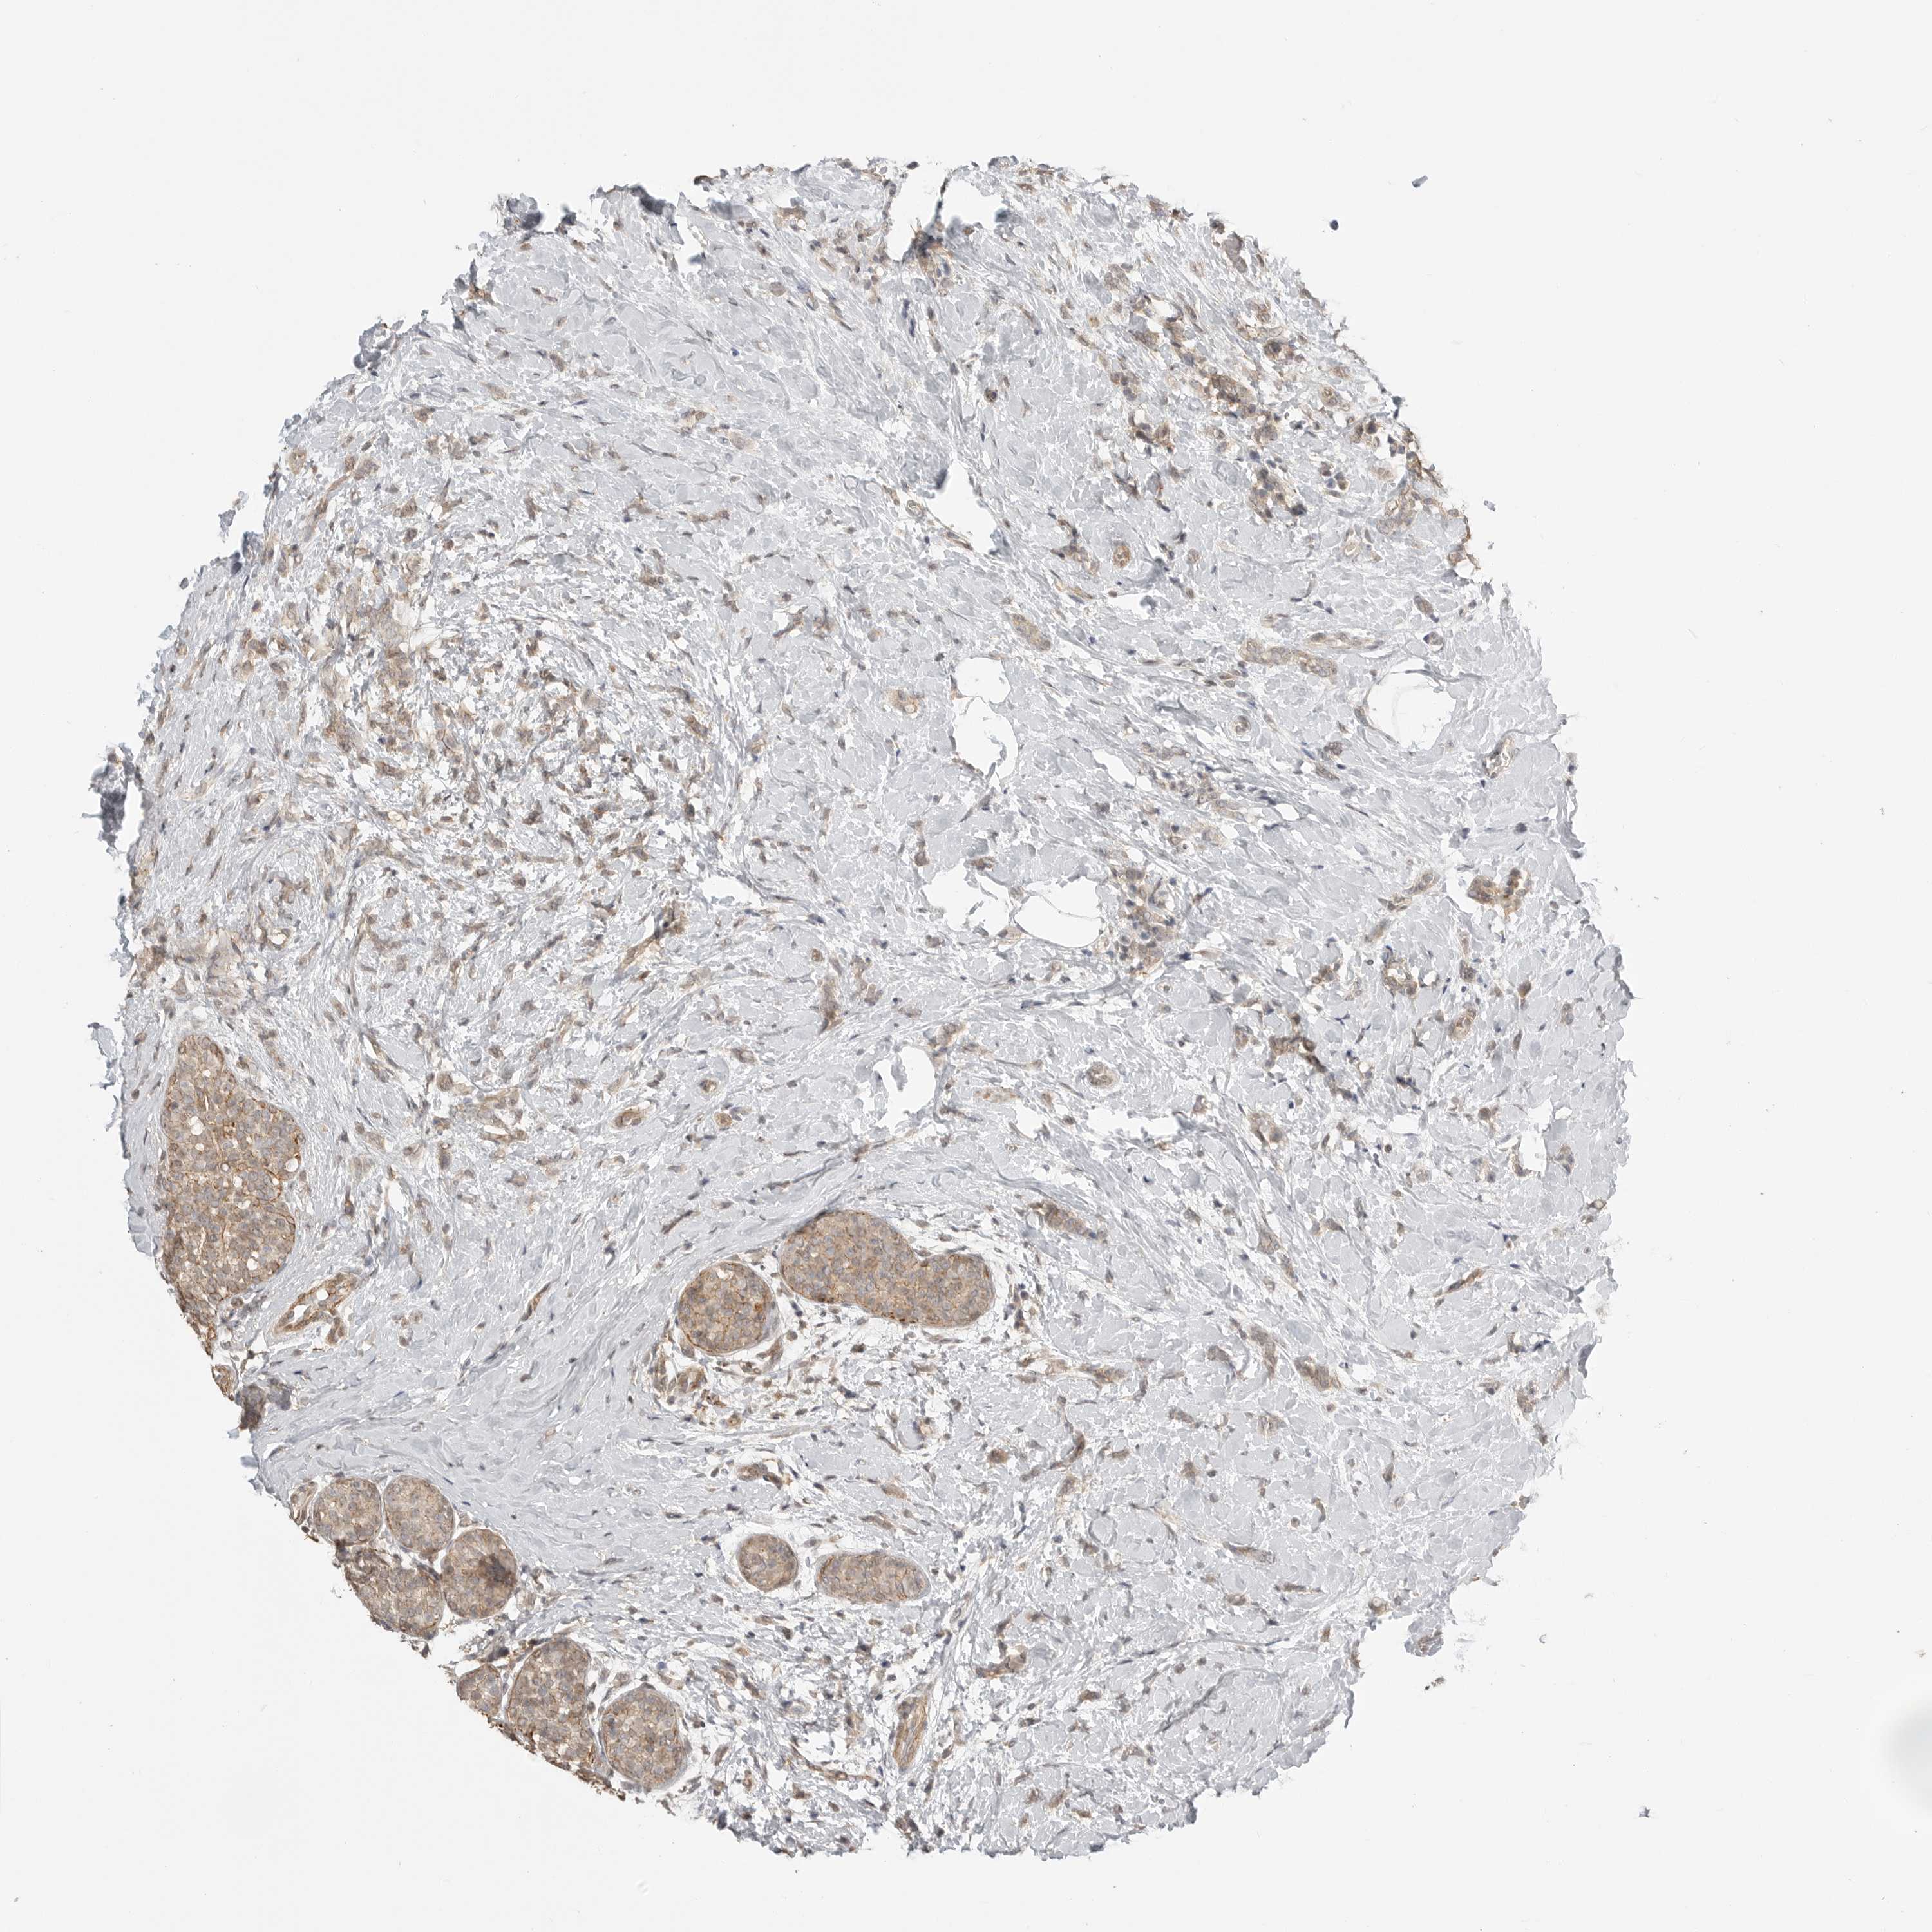

CANCER BREAST CANCER Show tissue menu

BRCA TCGA BRCA VALIDATION PROTEIN EXPRESSION